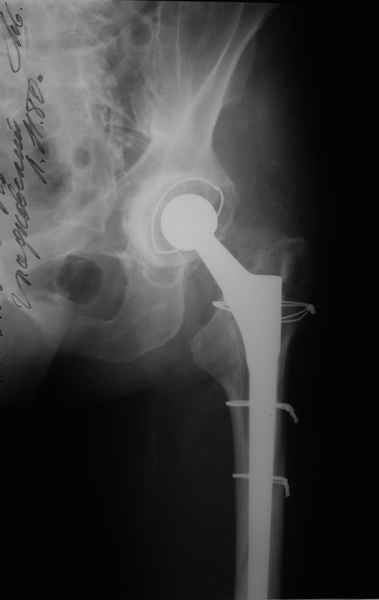

Уважаемые коллеги, продолжая дискуссию, начатую на "Вреденовских чтениях", хочу сказать, что принципиально сущестует два возможных варианта лечения.

1.Остеосинтез на ножке. Мне кажется, что применительно к этому случаю малоперспективный вариант. Синтез хорош, когда можно его выполнить в малоинвазивном исполнении и достигнуть стабильности. Действительно, если ножка б/цементной фиксации после этого не будет иметь фиксации, то ревизия не будет иметь проблем. В представленном случае стабильность синтеза сомнительная, а проведение доп.иммобилизации приведет к контрактуре суставов.

2. Применение ножки дистальной фиксации, мы отдаем предпочтение ножке Вагнера с фиксацией проксимального отдела на ножке. Более травматичное вмешательство, но при стабильной фиксации ножки реабилитация идет в обычном режиме.

Хочется показать два подобных случая, П-ка З. 72 лет и п-т Г. 80 лет. Сразу принимаю замечание, что это были ножки цементной фиксации, просто под руками не было бесцементника.